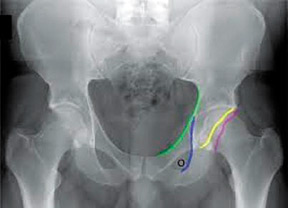

Interpreting the AP pelvic radiographs, however, can be difficult, and observing the anterior and posterior margins of the acetabulum is not always possible due to technique and quality of the radiograph. It has been observed that along with the crossover sign, the ischial spine is commonly projected into the pelvic cavity. This finding is easier to observe even when the crossover sign is not visible. Kalverer6 confirms that the crossover sign and the prominence of the ischial spine into the pelvis are reliable findings confirming the presence of acetabular retroversion.

Retroversion of the acetabulum is also associated with an externally rotated hemipelvis, which leads to protrusion of the ischial spine into the pelvis on the AP projection. COS and PRIS signs can be used to evaluate patients with early symptomatic femoroacetabular impingement and can also be used to detect hips at risk when the condition is bilateral, but only one side is symptomatic. The PRIS can be used even in pediatric cases because the acetabular walls are not ossified, so the contours are not visible on an AP radiograph.

Figure 3: Ischial spine is projecting (PRIS) into the pelvis on both sides.